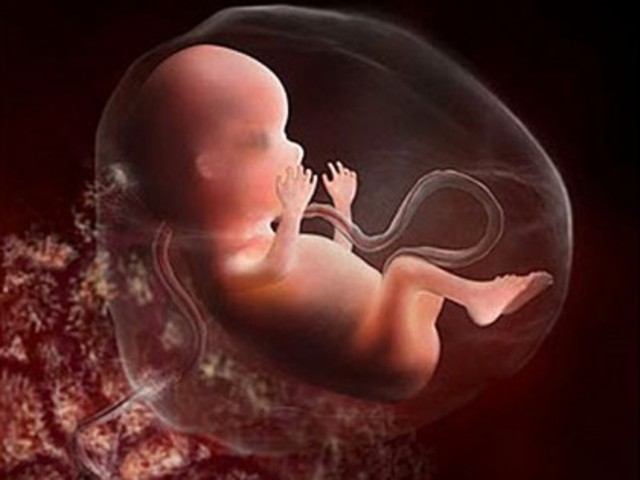

• week 24

week 24

Your baby's growing steadily, having gained about 4 ounces since last week. That puts him at just over a pound. Since he's almost a foot long (picture an ear of corn), he cuts a pretty lean figure at this point, but his body is filling out proportionally and he'll soon start to plump up. His brain is also growing quickly now, and his taste buds are continuing to develop.

http://www.babycenter.com/6_your-pregnancy-24-weeks_1113.bc